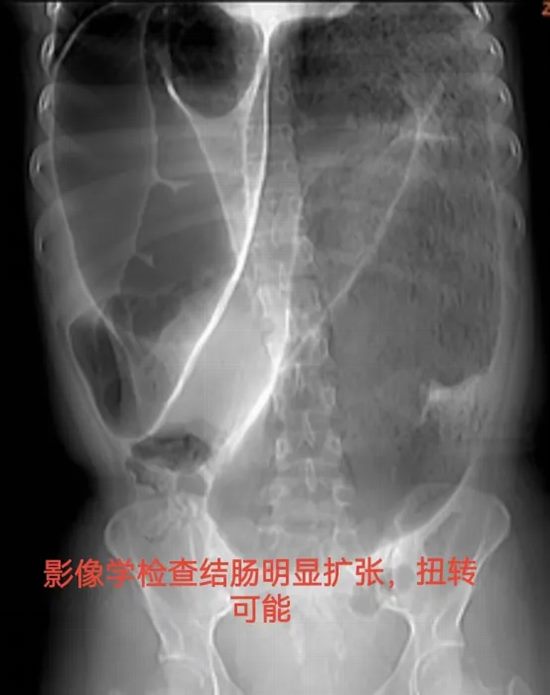

病情简述:19岁女性,间断腹痛腹胀4年,辗转求医未果。此次因急性加重急诊入院。

诊疗破局:CT提示结肠梗阻,非手术减压无效。急诊剖腹探查发现元凶是罕见的“结肠重复畸形”并扭转。及时的手术不仅解除了急性梗阻,切除了病变肠段,更找到了困扰她4年的病根。术后患者恢复良好,已回归正常生活。

技术体现:面对罕见急腹症,果断的手术决策与扎实的探查功底,是挽救患者、明确病因的根本。